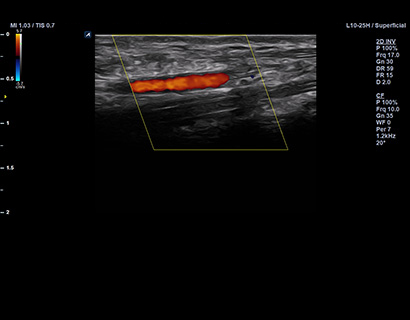

L10-25H

Wideband Ultra High Freq. Linear (10~25 MHz)

Application:

Vascular, MSK, Small Parts, EM